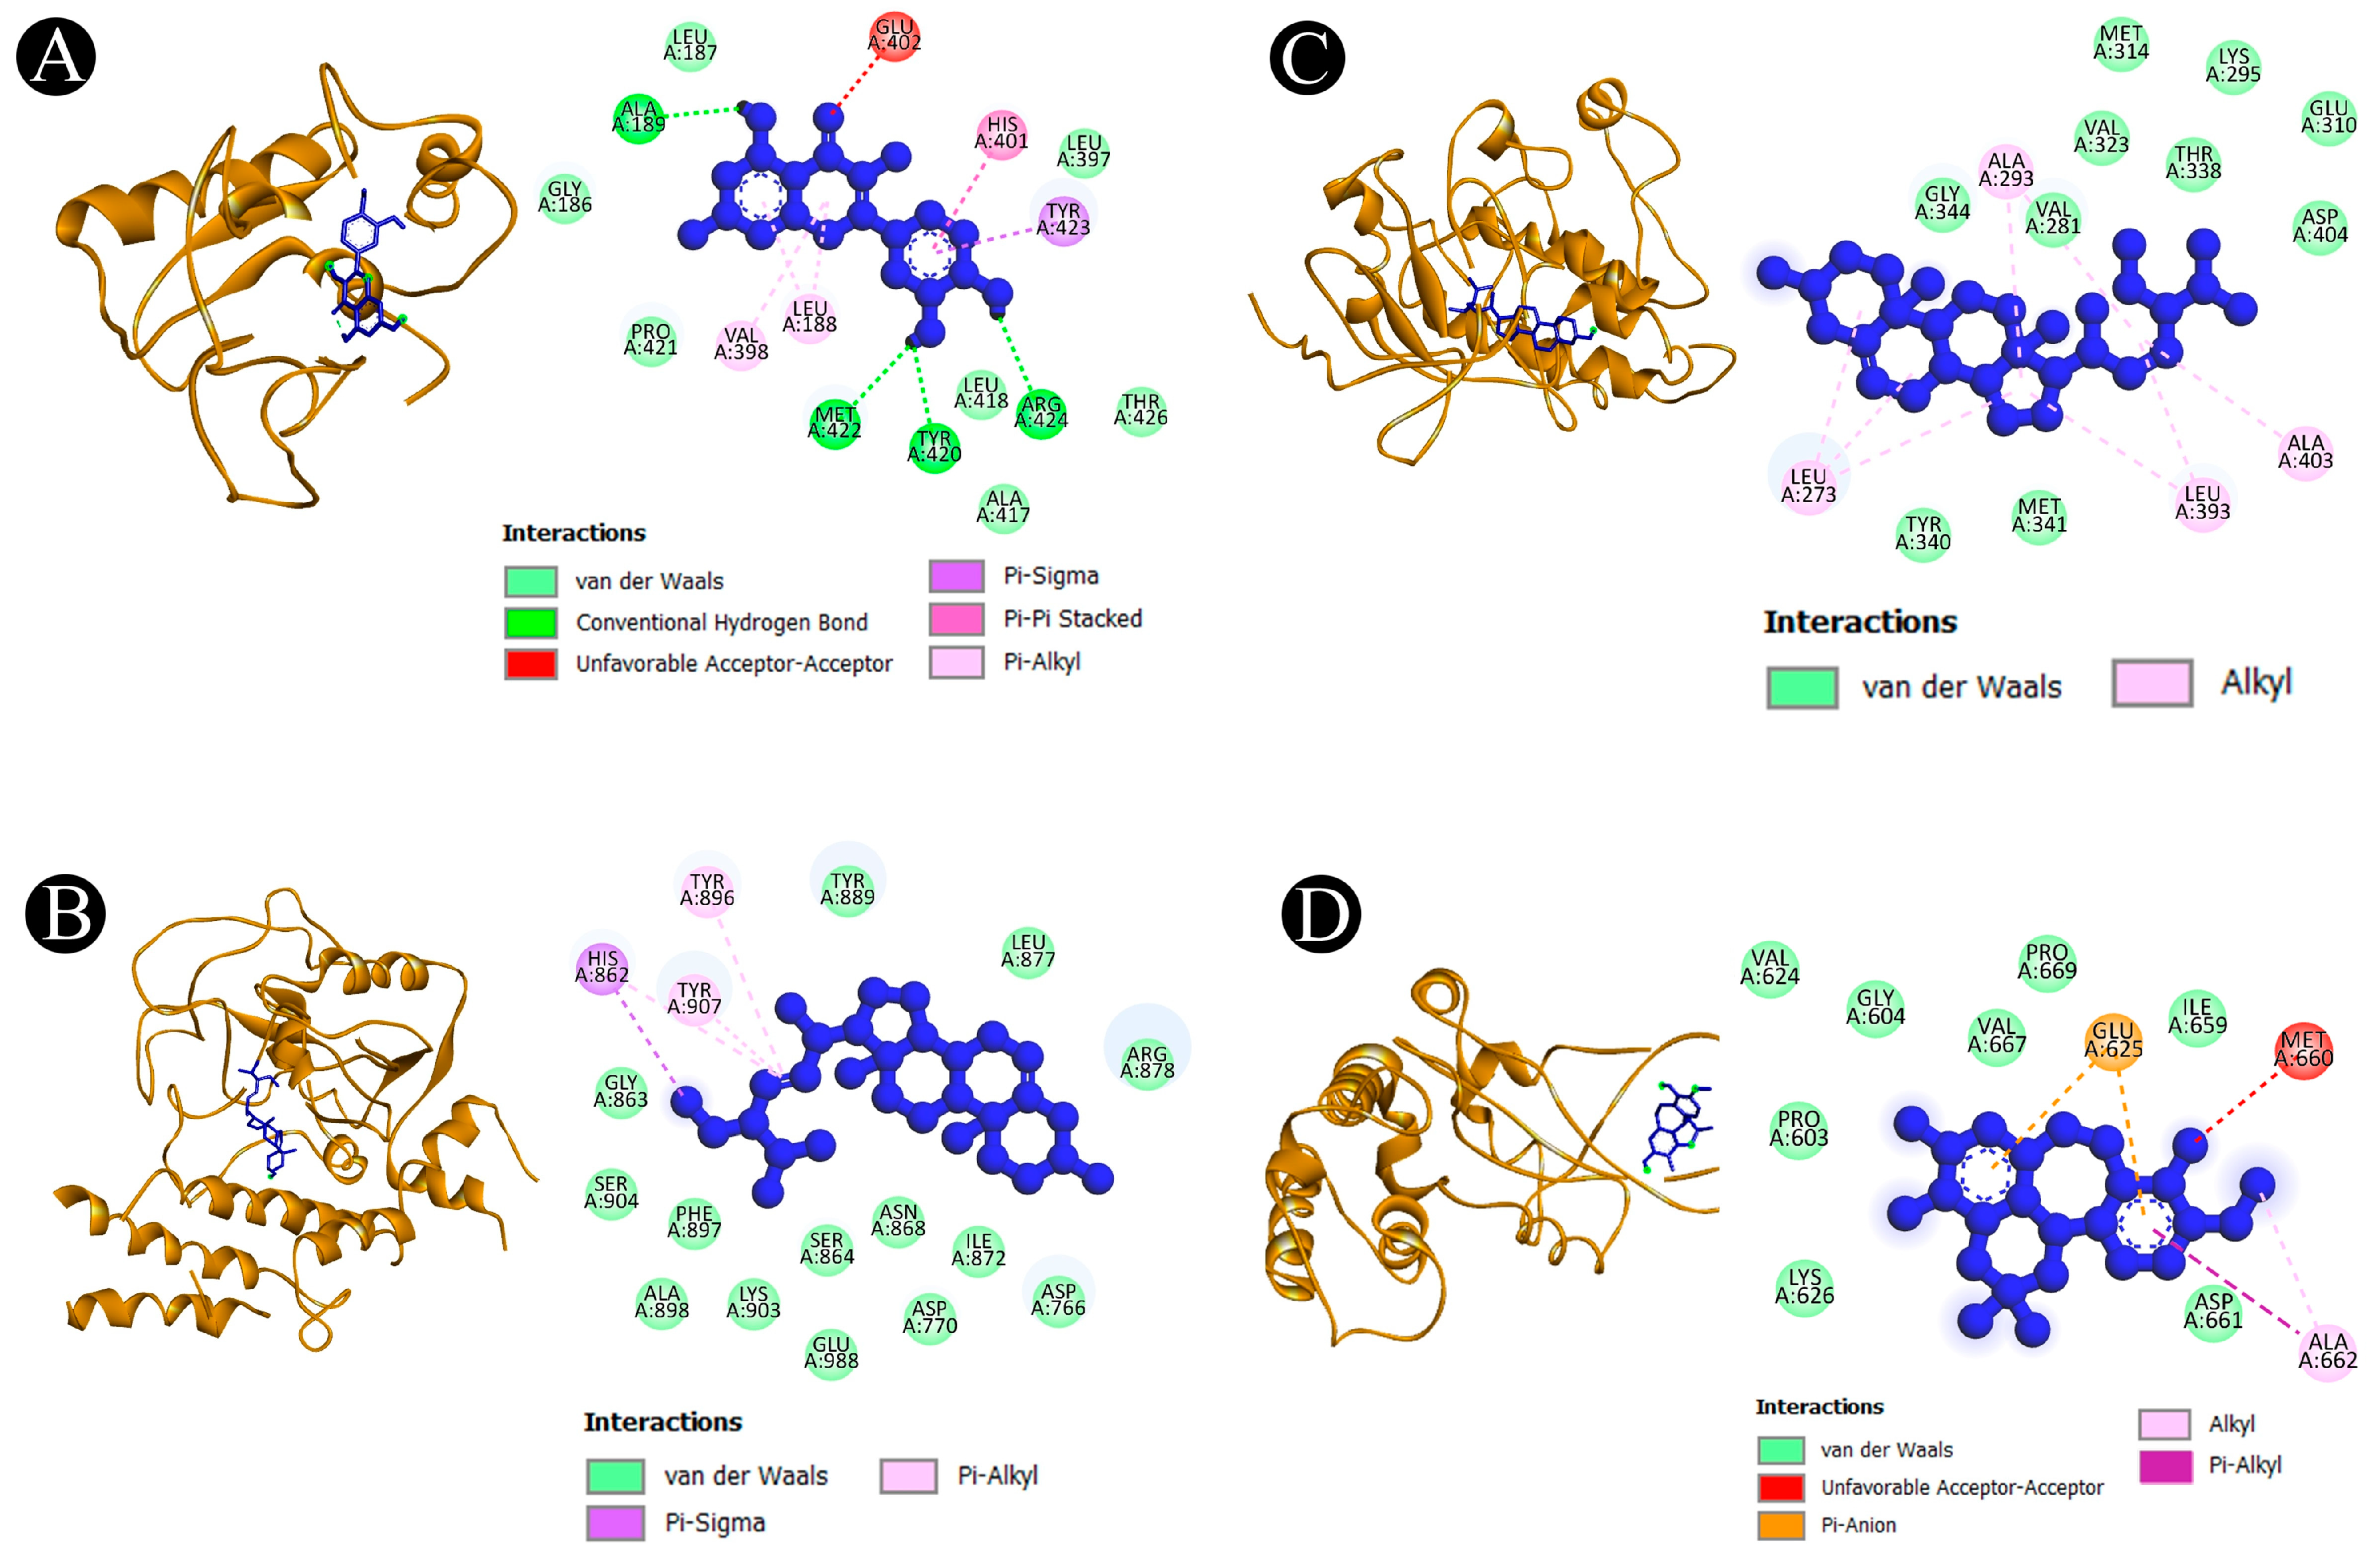

2.5. Binding Affinity and Molecular Interaction Analysis